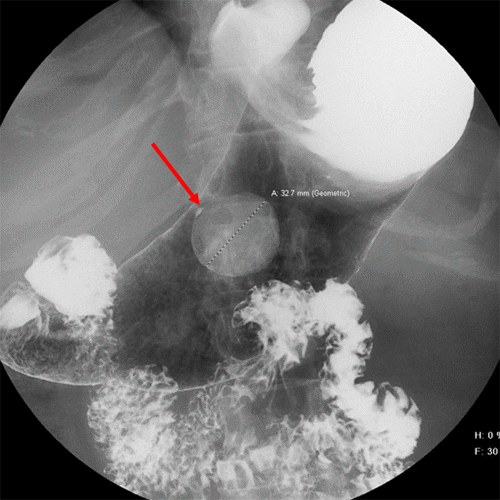

A 67-year-old female presented to the emergency department with abdominal pain and vomiting. She was referred to a gastroenterologist for an abdominal workup. She had an esophagogastroduodenoscopy (EGD, Figure 1) and CT (Figure 2) done, both showing evidence of tumor growth in her stomach.

Figure 1. Endoscopy Revealing GIST on Anterior Wall of Stomach. Published with Permission

A large sliding hiatal hernia was discovered on the EGD, which confirmed the size and morphology of the hernia. Additionally, the EGD revealed a 35 mm submucosal mass in the body of the stomach close to the pylorus on the anterior wall along the greater curvature. The patient's upper abdominal pain was mainly attributed to the hiatal hernia. The surgeon decided that during the hiatal hernia surgery, he would also address the tumor due to its malignant potential.